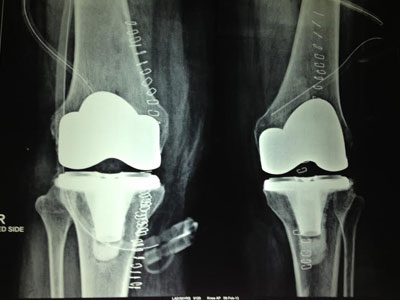

Total Knee Replacement is a procedure in which the parts of the bones that rub together are resurfaced with metal and plastic implants. Precision instruments are used to remove and replace damaged parts of the bone with implants. The surface of the femur is replaced with a rounded metal component that matches closely the curve of your natural bone. And the surface of the tibia/leg bone is substituted with a smooth plastic component.

Bone cement is used to secure the knee implants.